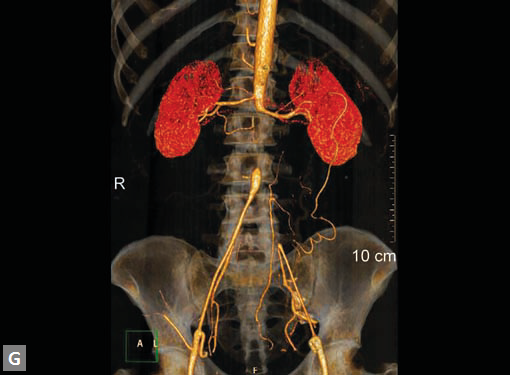

Figs 19A to Y (A to C) Scannogram (A), plain (B) and contrast study (C) show partial anomalous pulmonary venous connection; (D to F) Heterotaxy; (G) Aortic occlusion; (H and I) Aortic stents; (J) Aortic dissection with ‘Benz’ sign due to second dissection within the true lumen; (K, L and M) Aortic dissection with thrombus in pseudolumen following catheter angiogram; (N) Aortic dissection involving common carotid arteries and subclavian artery; (O, P, Q and R) Aortic dissection with right renal artery arising from true lumen and left renal artery from false lumen; (S, T, U and V) Stanford B dissection with extension Y to iliac vessels; (W to Y) Aneurysmal dilation of ascending aorta